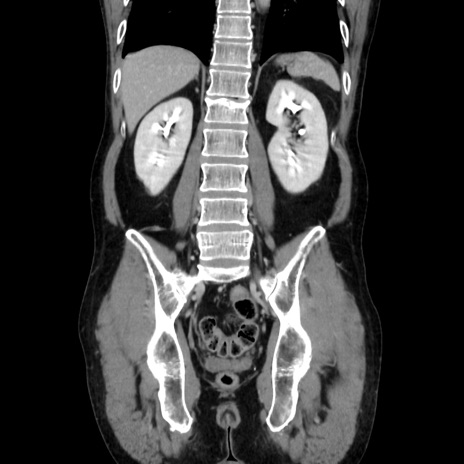

症例37(冠状断像)

【症例】40歳代 男性

【主訴】腹痛

【現病歴】4時間ほど前に電車に乗車中に臍部上より腹痛出現。徐々に増悪し起立困難となり、救急外来受診。生ものは数日食べていない。今朝お雑煮を食べた。

【身体所見】BT 36.8℃、BP 117/84mmHg、HR 91/min、SpO2 97%、苦悶様、腹部:臍上部広範囲圧痛あり、反跳痛±

【データ】WBC 8100、CRP 0.03